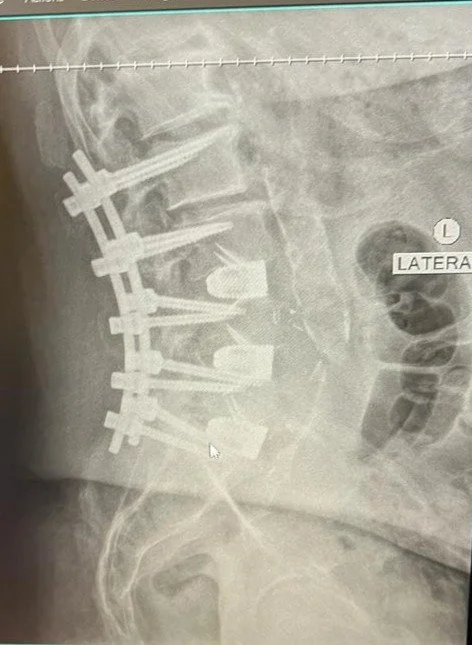

The Critical Role of Mind-Muscle Connection in Recovery After Spinal Fusion Surgery

This is one of my patients